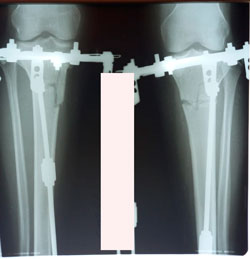

Исходник - 35 лет.

Дата операции - 15.01.2021

Анталия